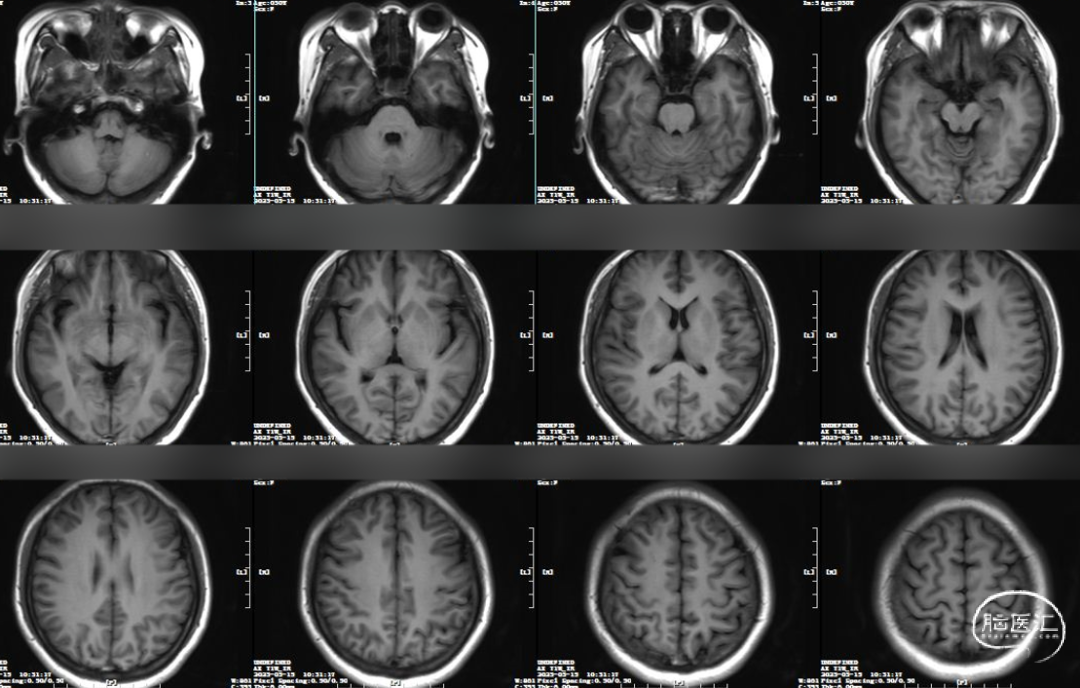

术前MRI(T1):未见明确静脉窦/静脉T1高信号影。

术前MRV:双侧横窦乙状窦交界重度狭窄。